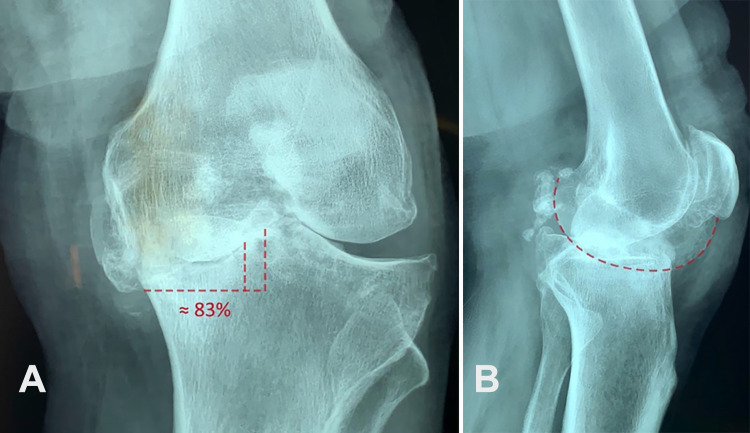

Results: 91 knees in 72 patients at 65.99±8.66 years of age and 8.28±2.58 years follow-up were studied. The tibial defects were managed with extra tibial cuts and adjustment of tibial component position in all, and the addition of structural autograft in 14 knees. 89 (98%) knees survived with a knee society score (KSS) of 79.4±17.6 and were significantly functioning well (P<0.001). Two knees required revision surgery. Significant improvement in outcome measurements was seen in all cases (P<0.001). No radiographic loosening, alignment change, or clinical instability was detected. The tibial plateau reconstruction without bone grafting and the ones that had autologous bone grafting had similar functional results and radiographic outcomes.

Conclusion: TKA with tibial defects of 15-25 mm treated with a semi-constrained posterior-cruciate ligament (PCL) sacrificing condylar prosthesis without any metal wedges or stem extensions with or without additional autogenous bone graft obtained very good functional and radiographic outcome and 97% survival in 6-17 years follow-up.